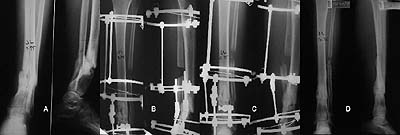

A,B) Finding the hinge point. C) Frame assembly. D) Correction.

A) Pre-op: Infected hypertrophic pseudarthrosis.

B) Frame assembly at the beginning of correction.

C) Frame assembly at the end of correction. 5 months in frame.

D) Final result.